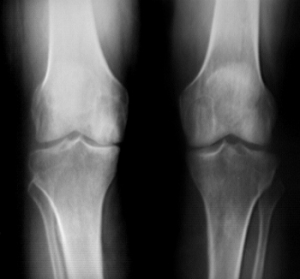

Radiological Testing

X-rays can help in the diagnosis and may be the only special test required in the majority of cases. X-rays can also help doctors rule out other problems, since knee pain from OA may be confused with other common causes of knee pain, such as a torn meniscus or kneecap problems. In some cases of early OA, X-rays may not show the expected changes.

Magnetic resonance imaging (MRI) may be ordered to look at the knee more closely. An MRI scan is a special radiological test that uses magnetic waves to create pictures that look like slices of the knee. The MRI scan shows the bones, ligaments, articular cartilage, and menisci. The MRI scan is painless and requires no needles or dye.